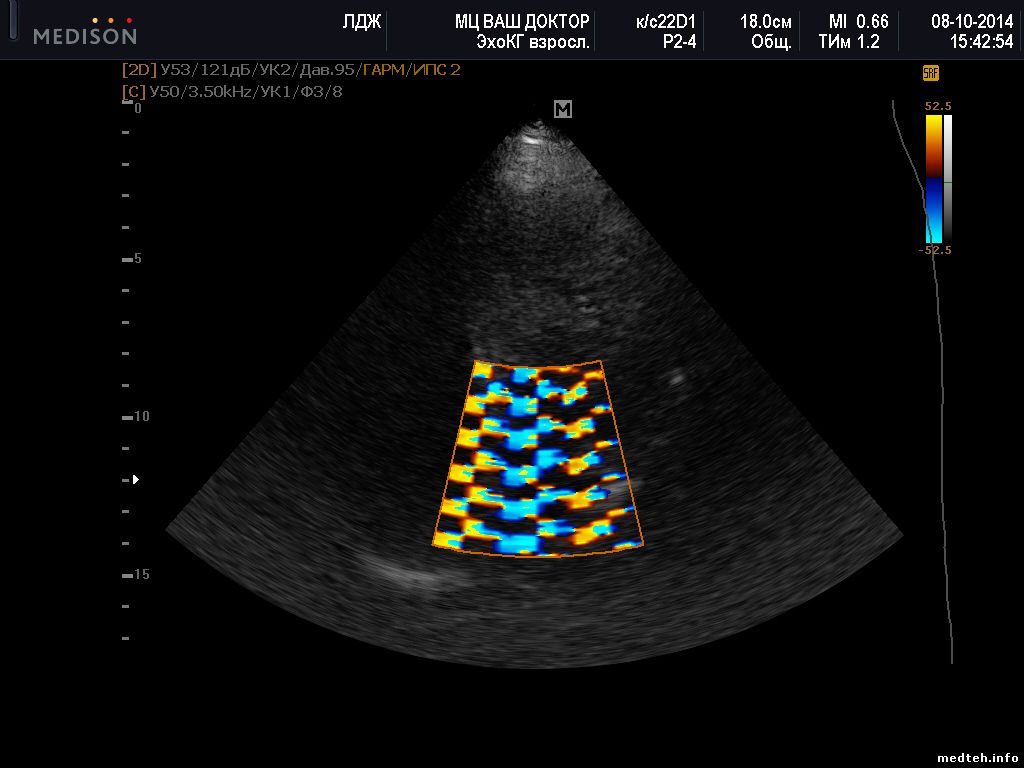

Здравствуйте! Помогите пожалуста кто чем может ) Sonoace X8 выдаёт картинку с помехами в режиме цветного доплера с настройкой TCD на кардио датчике P2-4AH. Причем на записи никаких помех нет. Покаывает вот такую картинку:

2583813.jpg(138Kb)

Здравствуйте! Что-то похожее и у меня. Сканер Sonoace R7, фазированный датчик P2-4AH. На кардиопрограмме при включении цветного допплера видим странную колористику, что на скриншотах в приложении. Также я записал клип https://yadi.sk/i/QQGNiI1UbznFv , на котором видна вертикальная "рябь" с определенной частотой. Исходные данные:

- сканер 2013 г.р., гарантия закончилась 5 месяцев назад

- подключен по схеме "сетевой фильтр" - "бесперебойник Schneider Electric", земляной провод в розетке, отдельного заземления нет

- ТО еще не проводилось

- проблема появляется хаотично (1 раз в неделю в течение 2-х недель раньше, на этой неделе второй день подряд)

- лечится тоже само и хаотично: врач посмотрит 20 - 120 минут других пациентов другими датчиками, потом проверяет фазированный - а он работает ;(

- остальные 2 подключенных датчика нормально работают во всех режимах, в том числе и в допплеровских

- переключение датчика в другое гнездо не помогает

- вчера проблему решило полное выключение и включение аппарата вместе с бесперебойником, сегодня уже не помогло

Прошу помощи и совета.

Очень похоже на программный сбой, особенно 2 картинка. При таких скоростях и частоте доплера на этом усилении изображение должно быть чистым. Попробуйте сменить режим цветного доплера на энергетический. Если при этом изображение нормализуется, то ПО. Если нет - вероятно датчик. Но я бы первым делом обновил ПО.